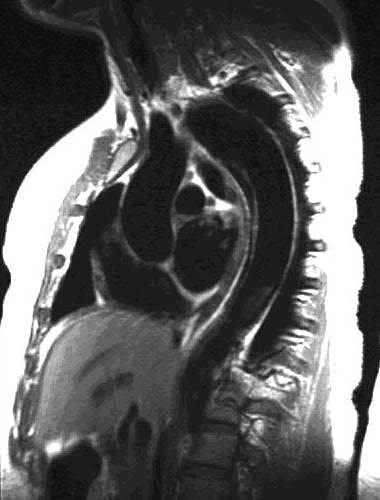

Type B Aortic Dissection:

Oblique sagittal SE images showing the flap originate adjacent to the origin of the left subclavian artery and

extending down into the abdomen: